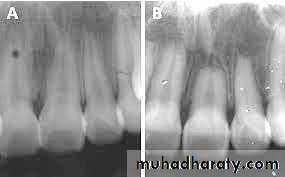

• Radiographic changes show:

– Chronic apical periodontitis in longstanding cases.

– In young patients, low grade longstanding irritation stimulates periapical bone deposition, i.e. condensing osteitis. Radiograph shows areas of dense bone around apices of involved teeth.